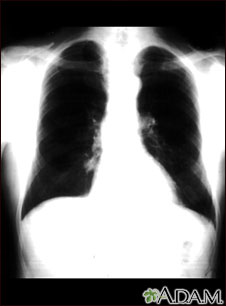

This is a chest x-ray showing a mass in the right lower lung near heart (seen on the left side of the picture).